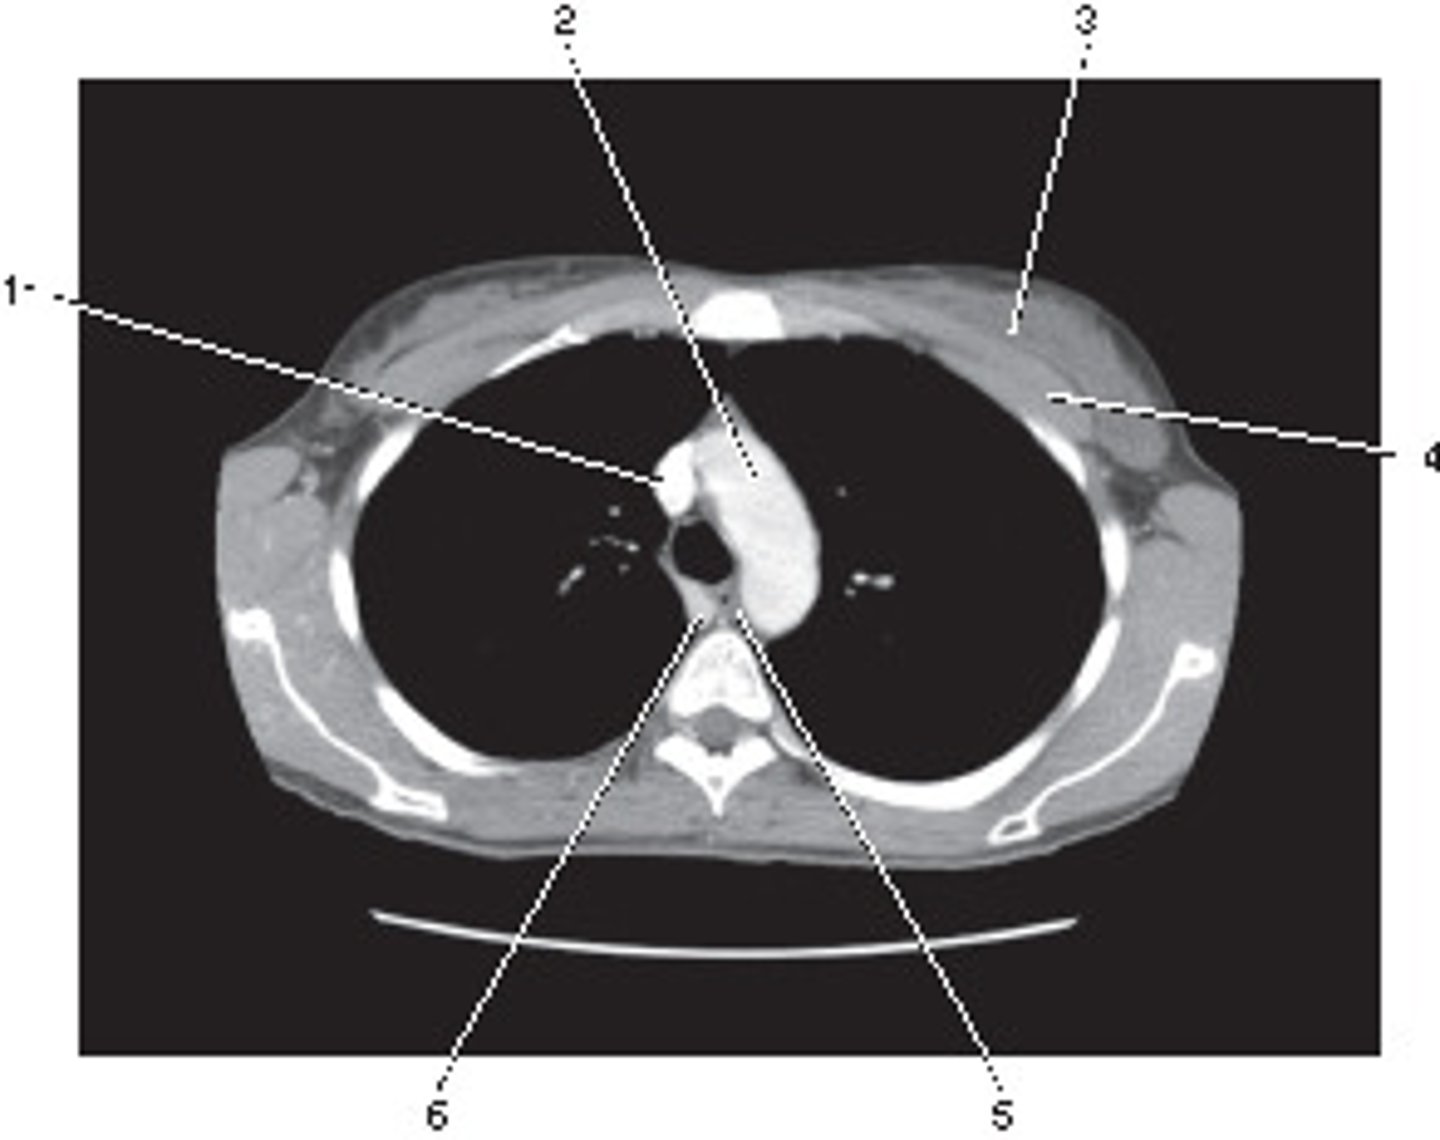

Descending Aorta

<p>Number 1 corresponds to which of the following?</p>

Aortic Arch

<p>Number 2 corresponds to which of the following?</p>

Azygous Vein

<p>Number 4 corresponds to which of the following?</p>

Right Brachiocephalic Vein

<p>Number 6 corresponds to which of the following?</p>

5

<p>Which number corresponds with the right atrium?</p>